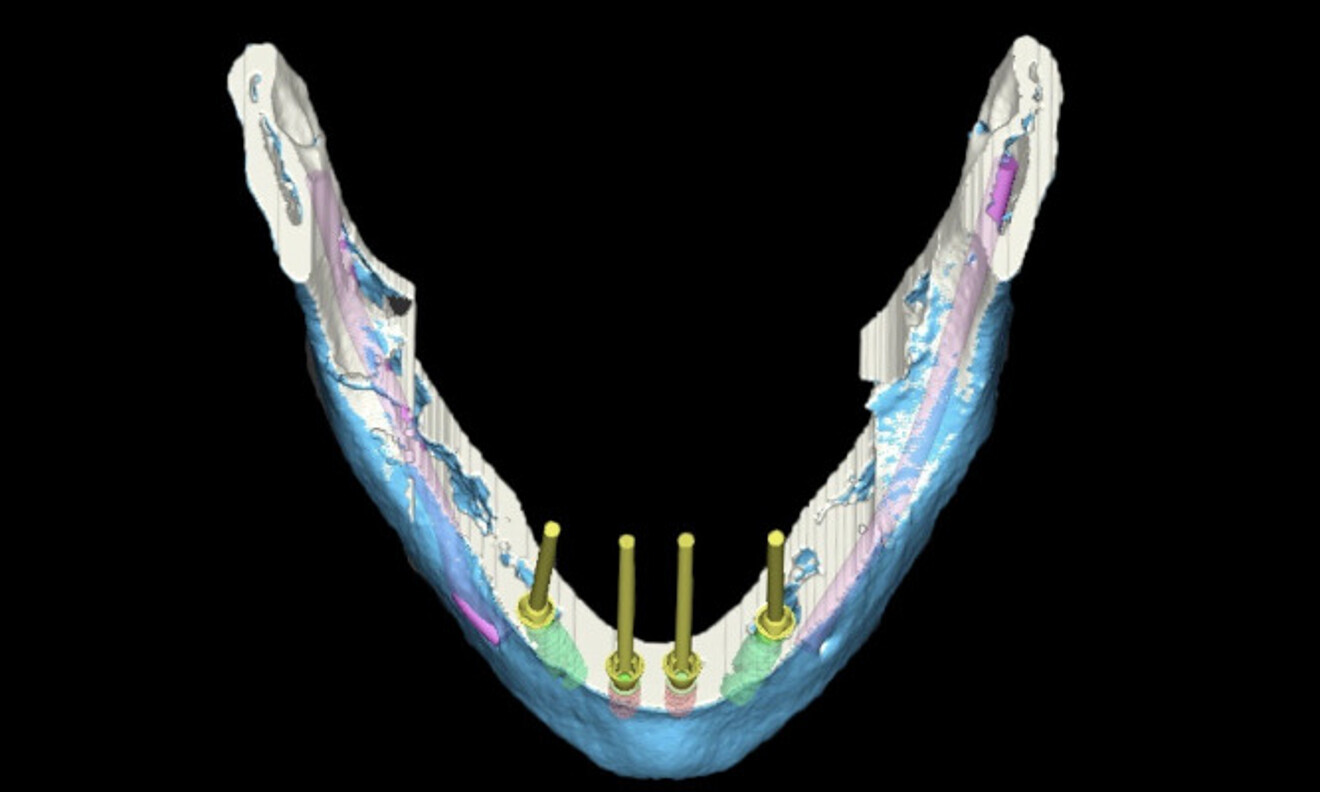

CoDiagnostiX software (Dental Wings) was used for planning the analogue surgical placement of two Straumann zygomatic implants and two Straumann BLX implants in the maxilla and of four Straumann BLX implants in the mandible. The protocol chosen was immediate placement after atraumatic extraction of the remaining teeth while protecting the remaining bone (Figs. 4 & 5). The patient’s STL file was generated and sent to the in-house laboratory to create a 3D-printed model for the surgical planning, allowing us to obtain a surgical model (Fig. 6).

Fig. 6